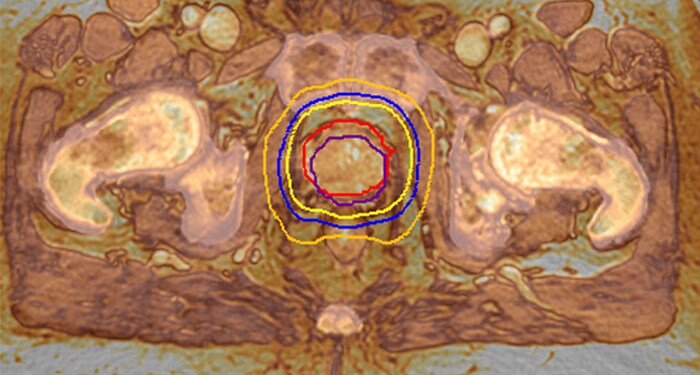

MR-RT XD meets the need for accuracy with advances in image quality, geometric fidelity, and reproducible patient positioning. You acquire high quality MR images in the treatment position, boosting accuracy in target delineation and critical structures.

Highly targeted treatment plans rely on MR imaging performed in the treatment position. With MR-RT XD you acquire high quality MR images in the treatment position, boosting accuracy in target delineation and critical structures.